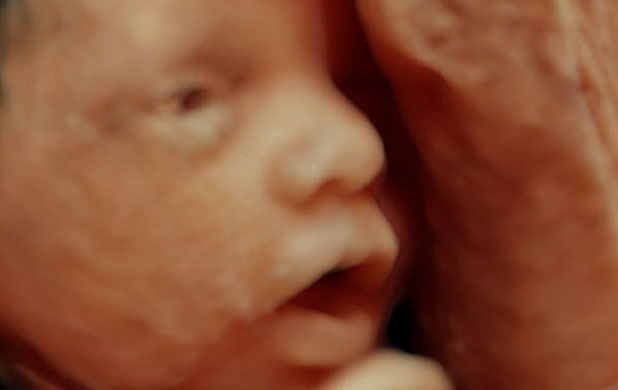

U medicini se ultrazvuk primjenjuje u dijagnostici

|